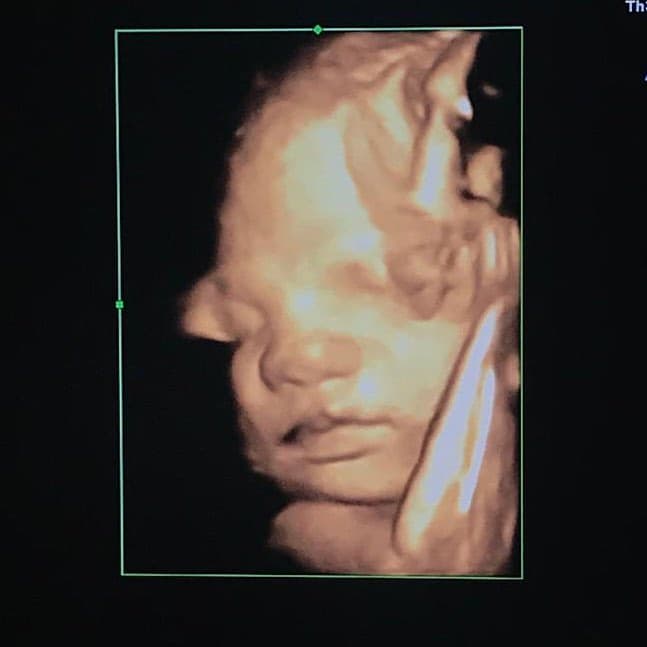

Ahora sí: Ingrid Martz pudo ver la cara de su bebé y esta fotografía lo prueba

Semanas atrás, la actriz se había mostrado ansiosa por conocer el rostro de su hija, fruto de su relación con Rodrigo Luque, pero la foto del ultrasonido no fue la ideal. Ahora sí pudo obtener una imagen de la carita de su bebé y lo compartió con sus seguidores.

Cuando cumplió 32 semanas de gestación, Ingrid Martz acudió a realizarse un ultrasonido con la esperanza de conocer la cara de su bebé.

En aquella ocasión, la actriz no lo consiguió y solo pudo ver un pie.

Y ahora que está a semanas de dar a luz, por fin pudo conocer la cara de su bebé.